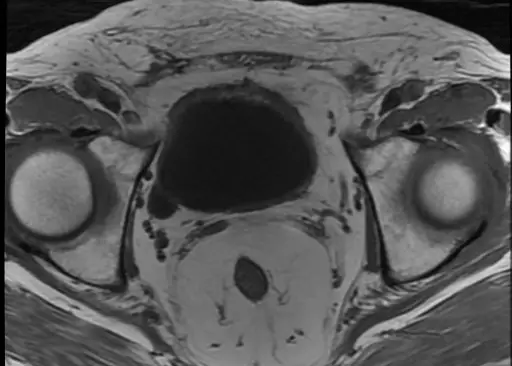

磁振造影檢查如下圖之影像,最可能為下列何種波序所產生?

本圖為骨盆腔的軸狀面(axial plane)磁振造影影像。我們可以觀察到幾個關鍵的解剖構造及其訊號表現:

- 膀胱(urinary bladder):位於影像中央前方,內部充滿尿液(游離水)。在此影像中呈現極明顯的低訊號(暗/黑)。

- 皮下脂肪(subcutaneous fat)與骨髓(bone marrow):影像外圍的皮下脂肪層以及兩側股骨頭(femoral head)內的骨髓,皆呈現高訊號(亮/白)。

- 骨骼肌(skeletal muscle):如骨盆周圍的臀部肌群及閉孔肌等,呈現中等訊號(灰)。

- (A) T1-weighted image:在 T1 加權影像中,水(尿液)的 T1 弛豫時間長,呈現低訊號(暗);而脂肪的 T1 弛豫時間短,呈現高訊號(亮)。此對比表現與本題影像特徵完全吻合,為正確選項。